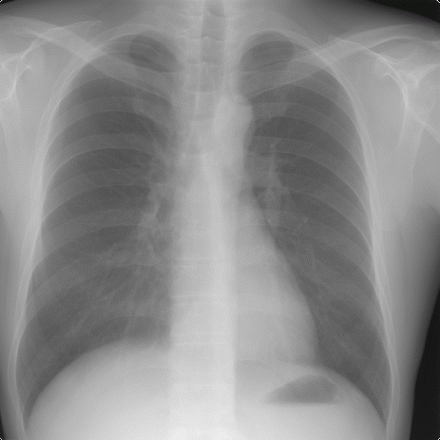

Röntgen Thorax

Die allseits bekannten Röntgenaufnahmen werden in unserer Praxis nicht mehr auf fotographischen Film, sondern digital auf sog. Festkörperdetektoren (CCD) aufgenommen, ähnlich einer Digital-Fotokamera.

Nun können die Bilder auf dem Bildschirm betrachtet, die Belichtung nachgeregelt werden, die Bilder elektronisch gespeichert oder versandt werden. Auf einem Laserfilmbelichter können die Bilder auch auf Folien ausgegeben werden, in der Regel werden sie aber digital, z.B. auf CD weitergegeben.

Die digitale Speicherung der Bilder gewährleistet, dass auch nach Jahren noch Kopien oder Bildvergleiche in Originalqualität möglich sind.